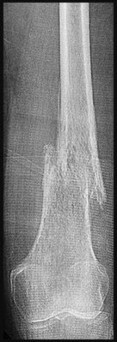

Question 9:

A 72-year-old female on prolonged bisphosphonate therapy presents with thigh pain. Radiographs show a fracture of the femoral shaft. Which of the following radiographic features is most characteristic of an atypical femur fracture associated with bisphosphonate use?

Correct Answer: Transverse or short oblique fracture line originating at the lateral cortex with localized periosteal thickening (beaking)

Explanation:

Atypical femur fractures (AFFs) associated with prolonged bisphosphonate therapy have specific major criteria defined by the ASBMR. These include a location anywhere from just distal to the lesser trochanter to just proximal to the supracondylar flare, transverse or short oblique orientation, non-comminuted (or minimally comminuted), and originating at the lateral cortex with localized periosteal or endosteal thickening ('beaking').